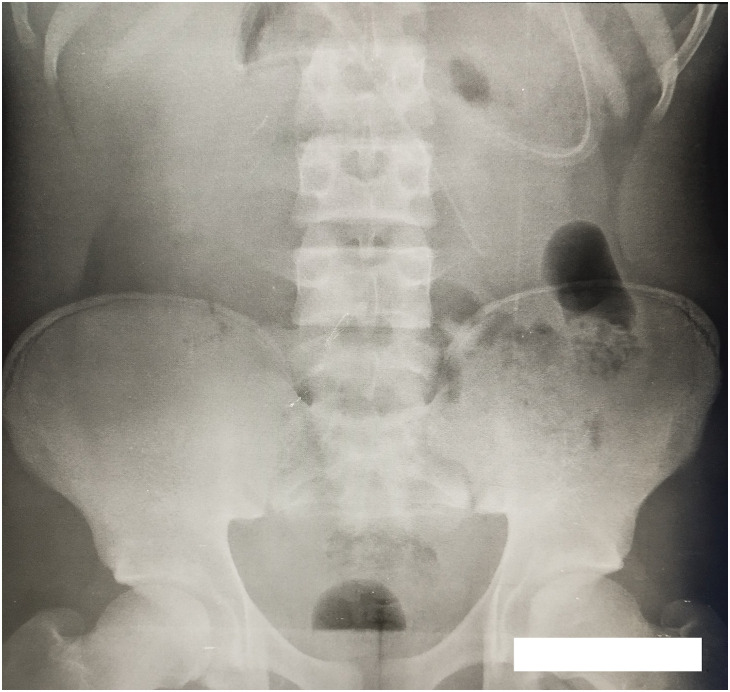

Case presentation: A 17-year-old black male student, with a body mass index of 28 kg/m2 was admitted to the emergency department of a 4th category rural hospital, with paroxystic abdominal pain and vomiting. Medical history revealed an abdominal surgery for an umbilical hernia 3 years earlier. There was no malformation such as imperforate anus, Hirschsprung's disease, esophageal tracheal fistula, or cardiac anomaly in the medical history. An abdominal X-ray confirmed an acute intestinal obstruction showing hydroaeric levels. The diagnosis of acute intestinal obstruction on a flange was retained. A median laparotomy was performed; a solid mass-like lengthy structure mimicking postoperative flange was seen associated with midgut volvulus, while a malposition of the intestine was observed with a mesenteric band, as well as a hyperemic appendix. A 90° rotation stop of the midgut also called a complete common mesentery was in place; we then carried out a Ladd procedure. Morpho-pathological examination of the surgical specimens revealed the following: richly vascularized fibro-adipose tissues with no evidence of malignancy in the diverticular specimen, and acute pan-appendicitis with no evidence of malignancy in the appendicular specimen. The patient started to ingest food orally on the third postoperative day, and he was discharged uneventfully on the fifth day.